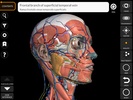

Nama Paket | com.catfishanimationstudio.MuscularSystemLite |

| Penerbit | Catfish Animation Studio | |